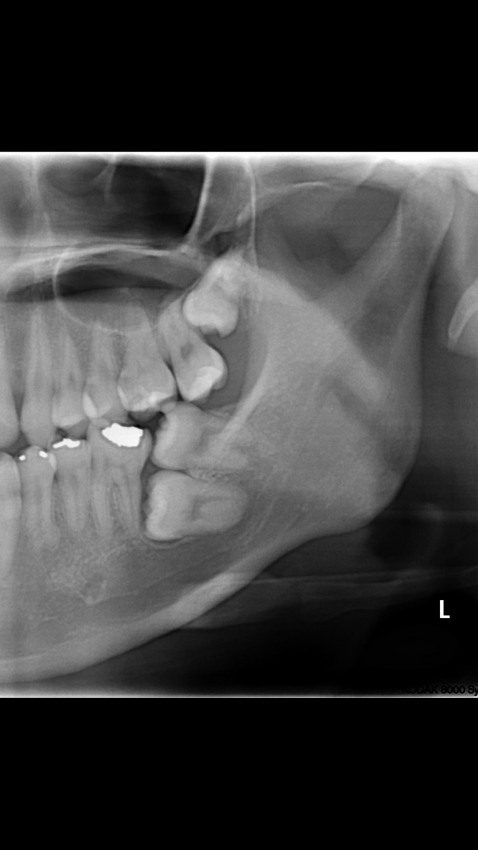

Subject   역대급 매복 사랑니

13136 역대급 매복 사랑니 15 요그사론 16/07/07 9137 0